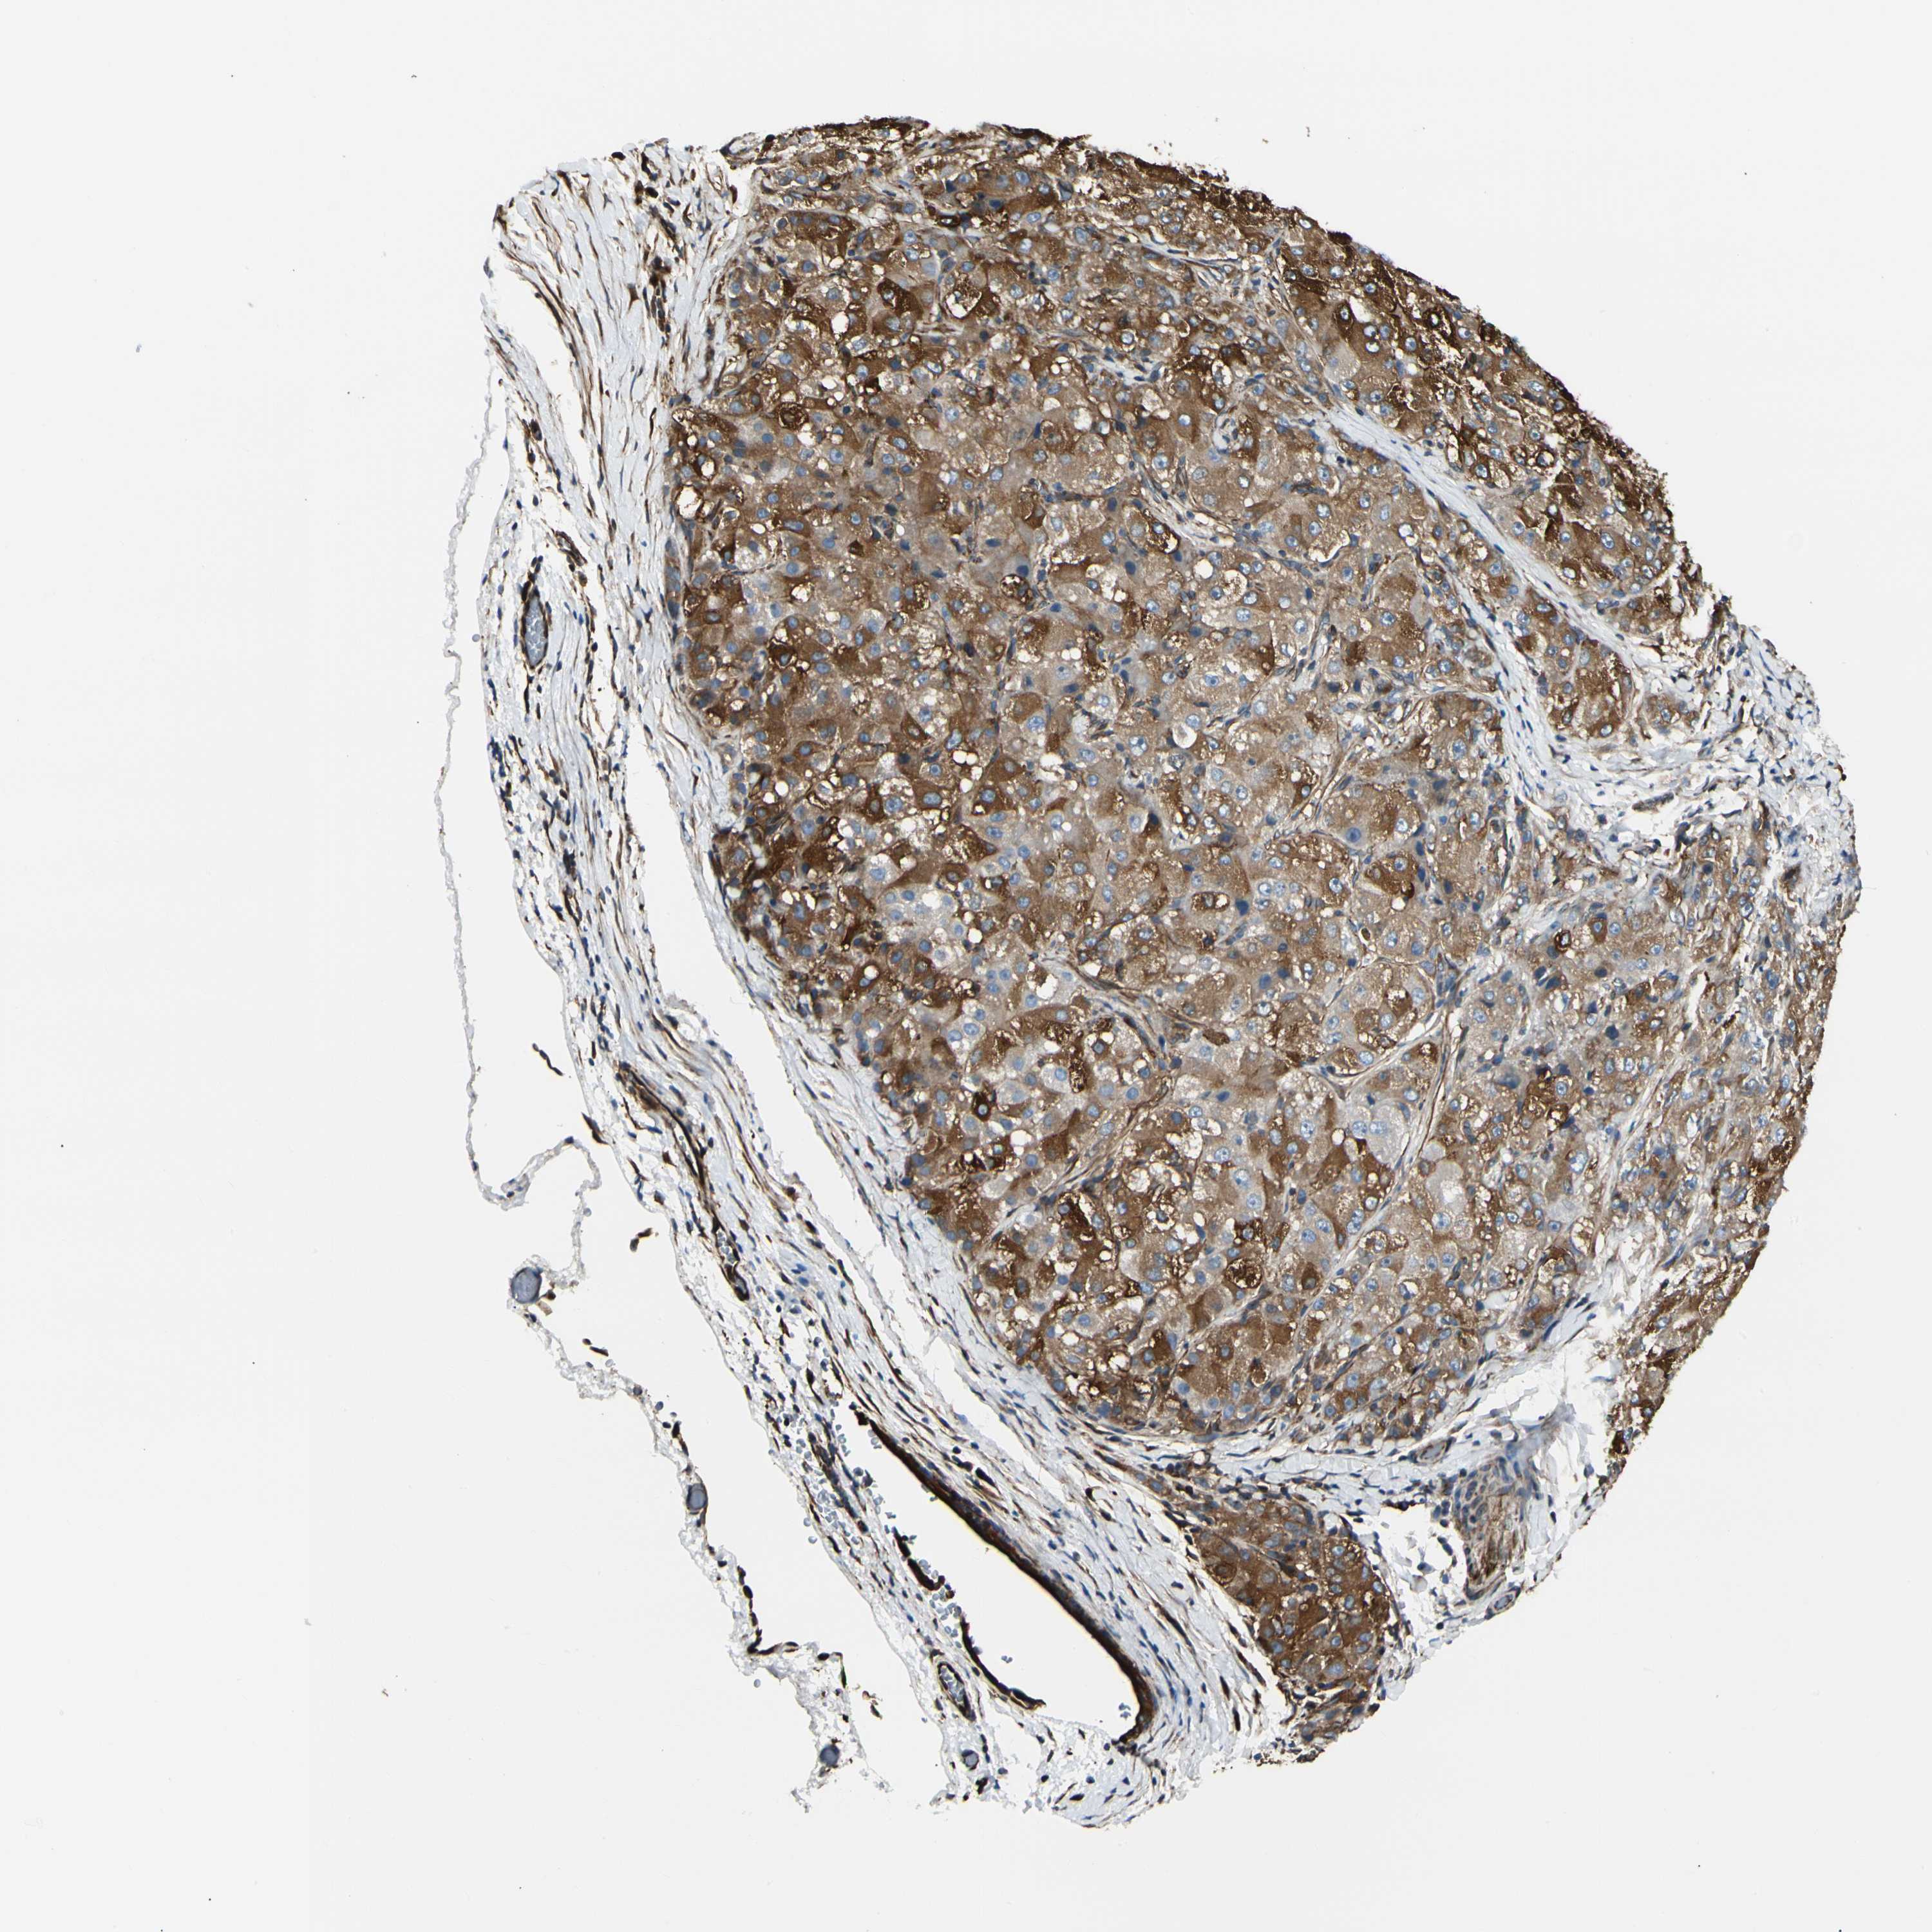

LIVER CANCER - Protein expressioni

A mouse-over function shows sample information and annotation data. Click on an image to view it in a full screen mode. Samples can be filtered based on level of antibody staining by selecting one or several of the following categories: high, medium, low and not detected. The assay and annotation is described here.

Note that samples used for immunohistochemistry by the Human Protein Atlas do not correspond to samples in the TCGA dataset.

Antibody stainingi

Antibody staining in the annotated cell types in the current human tissue is reported as not detected, low, medium, or high, based on conventional immunohistochemistry profiling in selected tissues. This score is based on the combination of the staining intensity and fraction of stained cells.

Each image is clickable and will lead to virtual microscopy that enables deeper exploration of all samples and also displays staining intensity scores, fraction scores and subcellular localization as well as patient and tissue information for each sample.

Antibody CAB008623

Staining

High

Medium

Low

Not detected

Intensity

Strong

Moderate

Weak

Negative

Quantity

>75%

75%-25%

<25%

None

Location

Nuclear

Cytoplasmic/membranous

Cytoplasmic/membranous,nuclear

Cholangiocarcinoma

Carcinoma, Hepatocellular, NOS